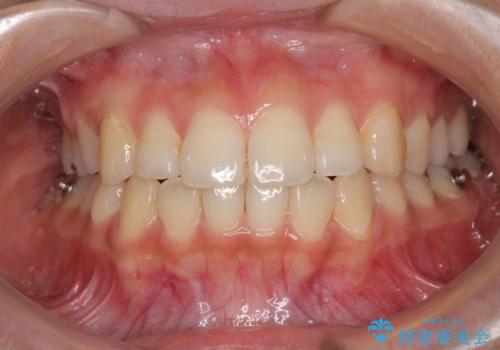

前歯の突出感とデコボコ インビザラインで改善

- 上下前歯のデコボコを気にして来院された患者様です。

インビザラインによる上下歯列の側方拡大と後方移動、IPR(歯と歯の間を削る)にるスペースの獲得により歯列を整えることとしました。

右上の小臼歯は歯根癒着をしており、様々な方法を試みるも動かすことができませんでした。

それでも奥歯のかみ合わせに不自由はなく、歯列をきれいに整えることができました。